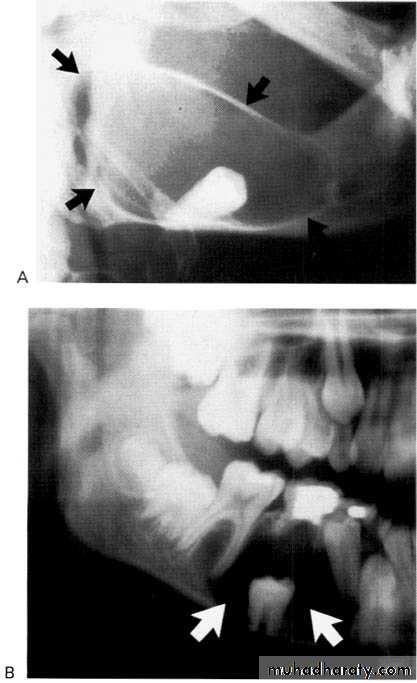

Displacement of teeth is seen more commonly with slower growing, space-occupying lesions.Lesions with an epicenter above the crown of a tooth (i.e., follicular cysts and occasionally odontomas) displace the tooth apically.

Cherubism originates and grows in the mandibular ramus, it has a propensity to push molars in an anterior direction.

Some lesions (e.g., lymphoma, leukemia, Langerhans’ cell histiocytosis) grow in the papilla of developing teeth and may push the developing tooth in a coronal direction